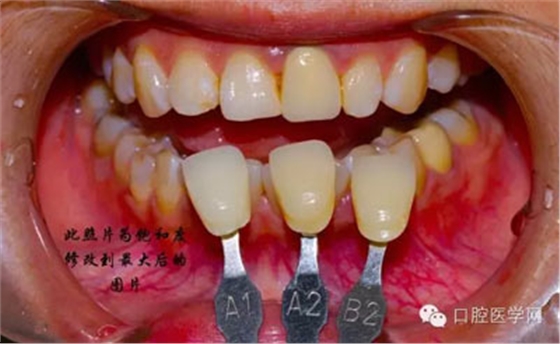

將比色照飽和度調(diào)到最低有助于牙齒明度的選擇

將比色照的飽和度調(diào)到最高有助于牙齒道飽和度選擇